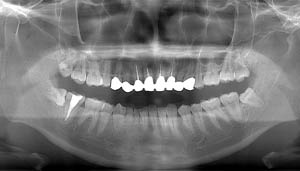

左上下の親知らずが

大きな虫歯になっていた症例

- 抜歯前写真(レントゲン)

- 抜歯前写真(CT画像)

| 年齢 | 20代・男性 |

|---|---|

| 主訴 | 奥歯が欠けて、痛みがある |

| 親知らずの生え方 | 完全に出ている、まっすぐ生えている |

| 抜歯時間 | 30分 |

| 費用 | 約5,000円 |

| 抜歯内容 | 奥歯が欠けて痛みがあるとのことで来院された患者様です。左上下の親知らずが大きな虫歯になっており、神経まで達している状態でした。上下ともに歯の頭部分は虫歯で脆くなっていたため、できるだけ根の部分の方に器具を引っかけて抜歯を行いました。 この症例では事前にCTを撮影し、歯の位置、根の方向、上顎洞との位置関係を確認していたため、上顎洞への穿孔や下顎の神経麻痺など後遺症も起こりませんでした。 抜歯後はほとんど腫れ、痛みはなく元々あったお痛みもなくなり患者様も安心しておられました。 |